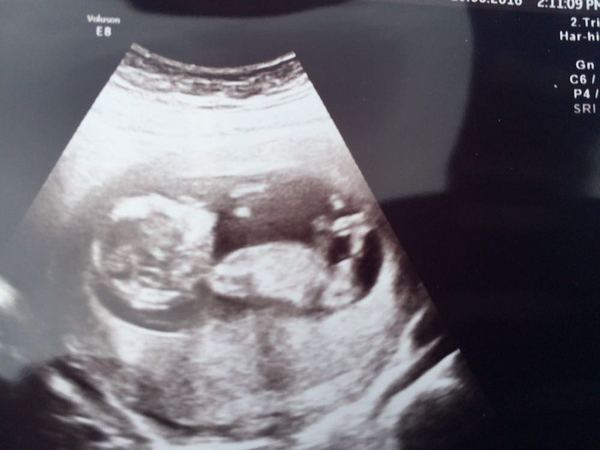

FluffyPickleMonster · 10/06/2016 18:17

Successful scan here today! Meet mini monster! Very wriggly and doing somersaults! NT measurement was 1.9, so low risk but awaiting bloods. All as it should be, moved me forward one day so now due 17th dec instead of 18th. One day closer, hurrah!